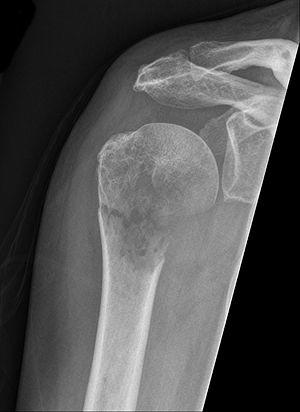

Pathologische Fraktur bei Metastase Nierencell-Ca im Humerus.jpg

Pathological fracture of the humerus in a patient with metastasis of renal cell carcinoma

A pathologic fracture is a bone fracture caused by weakness of the bone structure that leads to decrease mechanical resistance to normal mechanical loads.[1] This process is most commonly due to osteoporosis, but may also be due to other pathologies such as: cancer, infection (such as osteomyelitis), inherited bone disorders, or a bone cyst. Only a small number of conditions are commonly responsible for pathological fractures, including osteoporosis, osteomalacia, Paget's disease, Osteitis, osteogenesis imperfecta, benign bone tumours and cysts, secondary malignant bone tumours and primary malignant bone tumours.

Pathological fractures present as a chalkstick fracture in long bones, and appear as a transverse fractures nearly 90 degrees to the long axis of the bone. In a pathological compression fracture of a spinal vertebra fractures will commonly appear to collapse the entire body of vertebra.